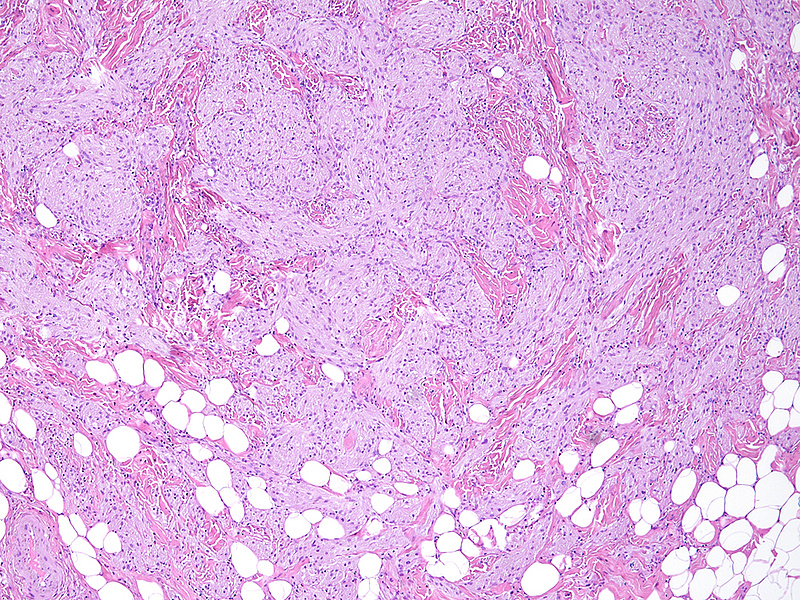

Histologically, we saw a submucosal proliferation of solid nests and ribbons of round to polyhedral cells, measuring approximately 6 mm in largest diameter (Panels A-B). The neoplastic cells generally contained small, uniform nuclei with inconspicuous nucleoli and abundant granular eosinophilic cytoplasm. They were separated by fibrous septa, which contained few inflammatory cells, mostly lymphocytes and few eosinophils (Panel C). In some areas, the neoplastic cells demonstrated cell spindling, still keeping the cytoplasmic features described above (Panel D). The lesion was ill-defined at the base, showing an infiltrative pattern into the surrounding adipose tissue within the submucosal layer (Panels E-F). The neoplastic cells were positive for PAS and strongly immunoreactive for S100-protein (Panels G-H), yet negative for keratin, CD117, DOG-1, and muscle markers, prompting final diagnosis of colonic granular cell tumour.